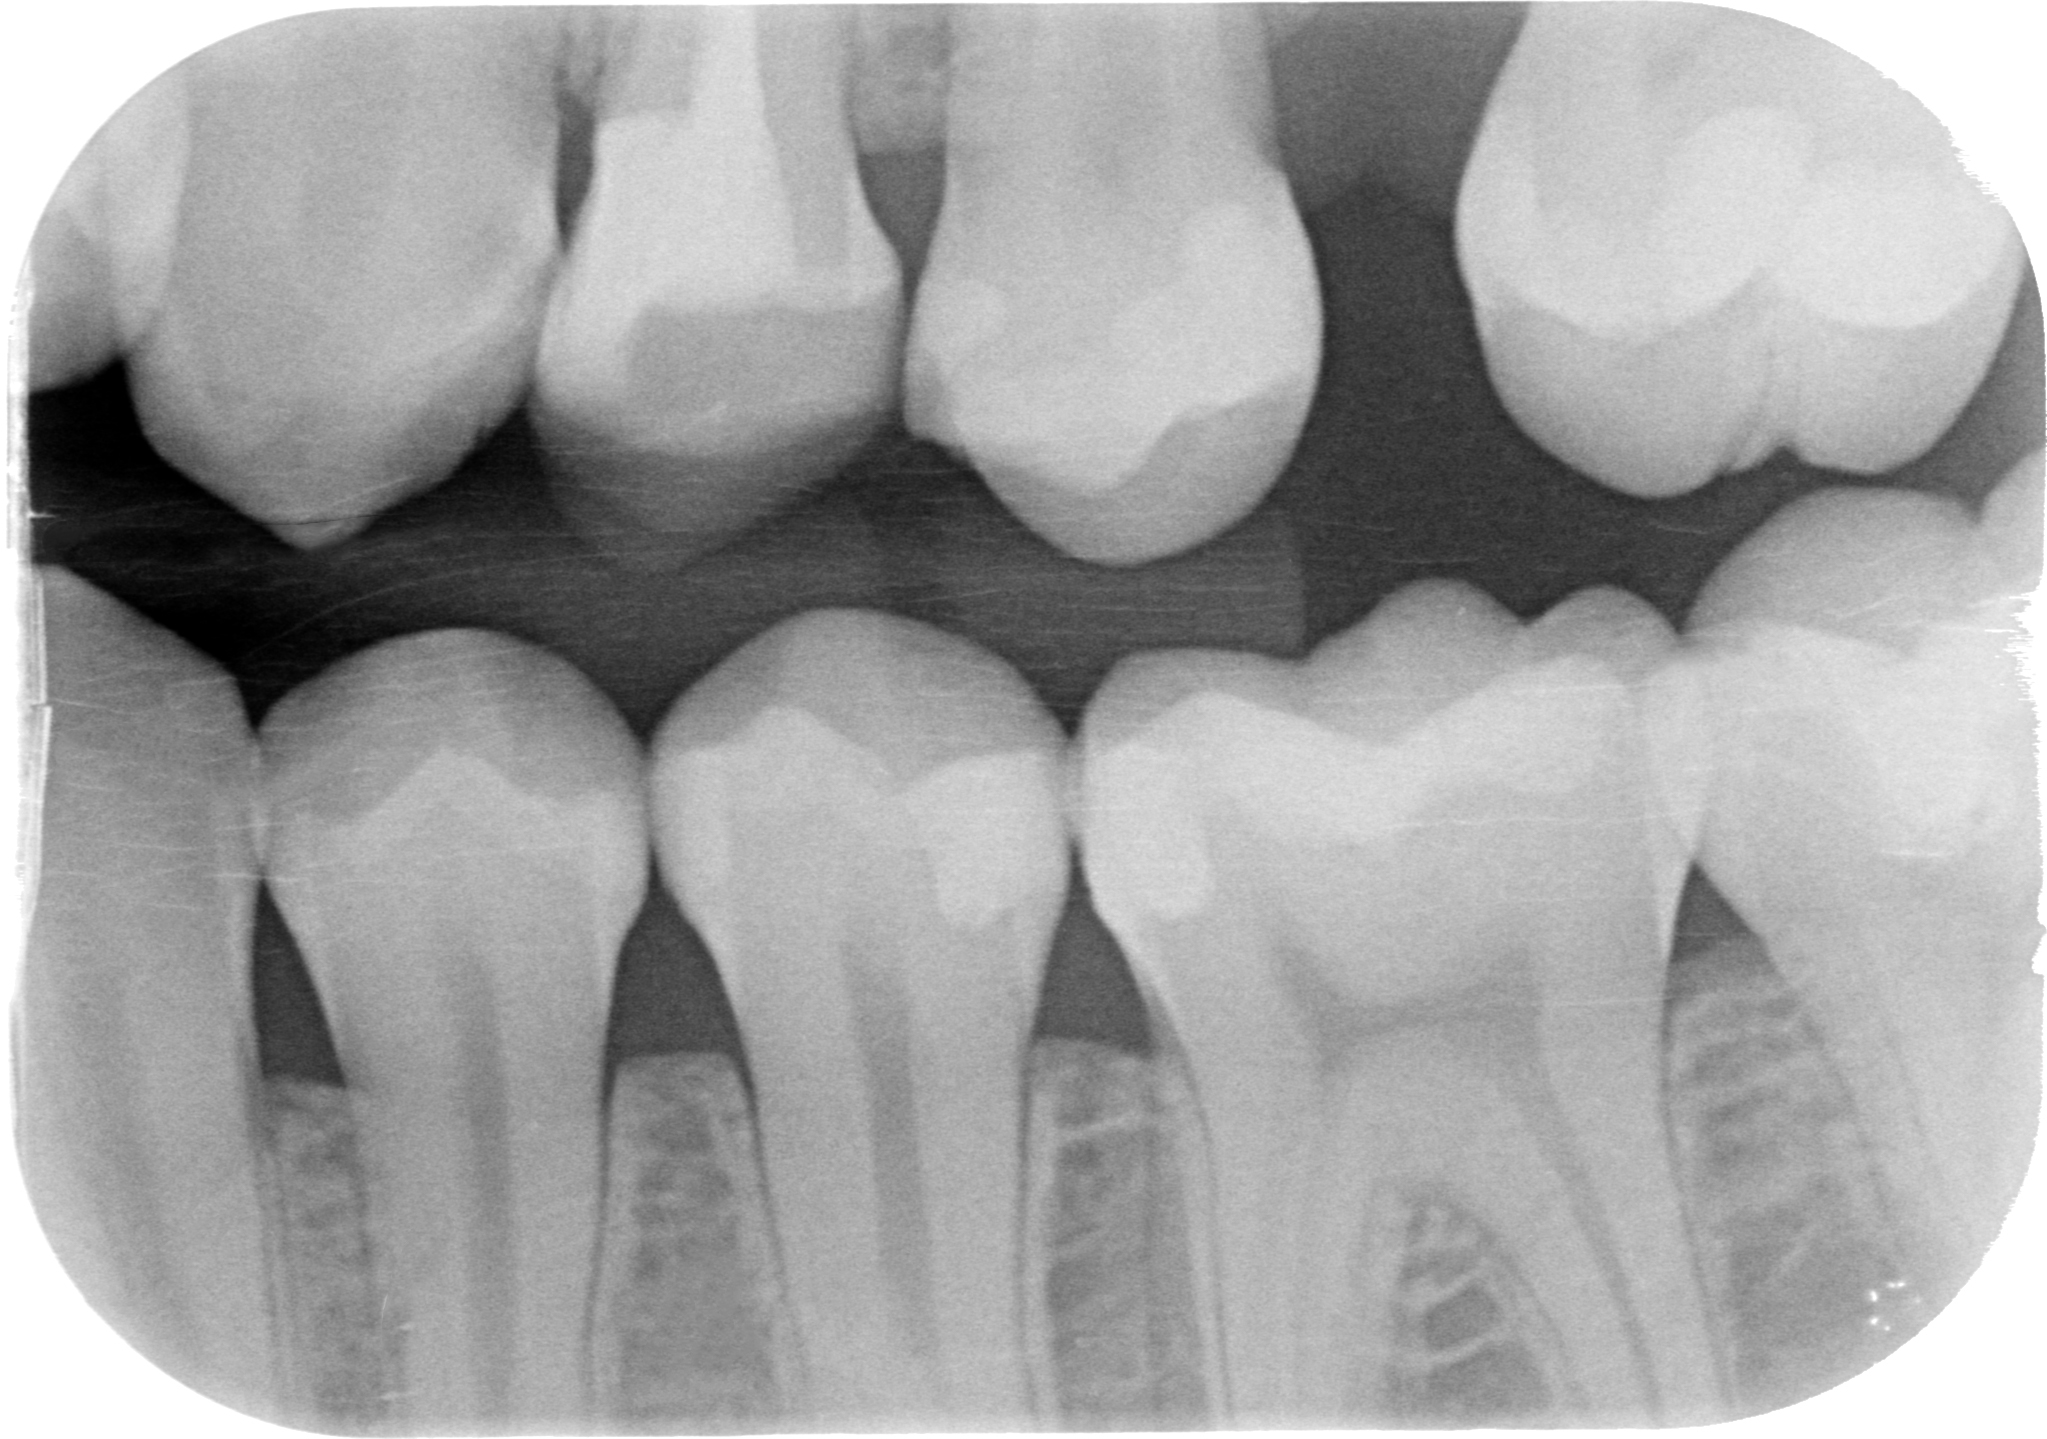

Se invadere l’ampiezza biologica massacra l’osso e genera tasche spiegami perchè in queste due rx scattate a 4 anni di distanza tra loro, l’osso distale al 4.7 mesializzato, che sarà da estrarre per altri motivi, sia sempre uguale, con un risentimento legato alla carie primaria che c’era stata verosimilmente decenni prima…?

Sappiamo che in questi casi l’osso interprossimale a volte è ancora intonso, in altri si è già ritirato per l’impatto cronico di cibo che spesso accompagna queste lesioni.

Come puoi vedere dalle immagini qui sotto, il caso che ho mostrato nella rx precedente a 4 anni di distanza mostra che nè l’osso nè la papilla risentono di questo terribile insulto…